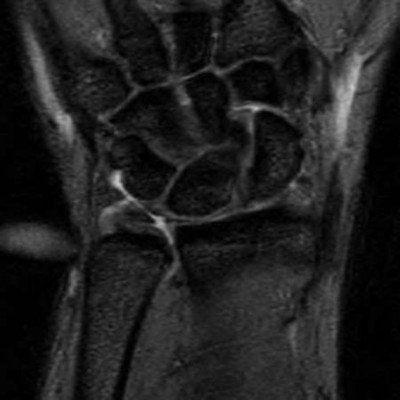

A 20-year-old park ranger trips and falls onto his right wrist with the wrist in extension and pronation. The local urgent care orders both radiographs and a CT, which you review and determine to be normal. The patient complains of ulnar-sided wrist pain. On exam, his tenderness is localized to the fovea. Ulnar deviation also causes him pain. There is no snapping sensation with wrist supination, flexion, and ulnar deviation. He otherwise has 5/5 strength to his first dorsal interosseous muscle with 4mm static two-point discrimination on the ulnar side of the 4th digit. Which of the following injuries is most likely responsible for his symptoms and exam?